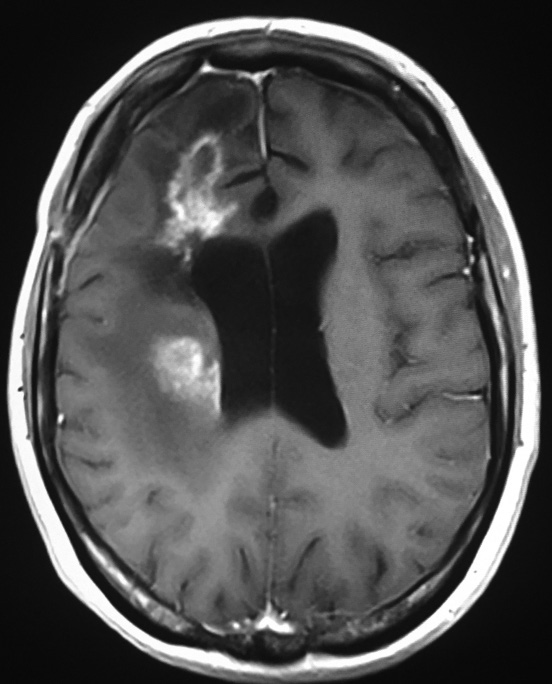

Así como la forma de pseudotumor de la esclerosis múltiple (43), hay otras formas tumorales con aspecto de granulomas, como se observa en otras infecciones bacterianas, micóticas, parasitarias, a cuerpo extraño (44), entre otras. En el diagnóstico diferencial se debe tener en cuenta la neoplasia, el absceso, la hematoma en reabsorción y la radionecrosis (26).

En la figura 8, se aprecia una imagen de RM en corte axial en T1-W y con gadolinio de cerebro, que muestra dos lesiones captadoras en anillo irregular e incompleto, rodeadas de edema y adyacentes a la pared ventricular en el lóbulo frontal derecho, correspondientes a formas pseudotumorales de esclerosis múltiple.